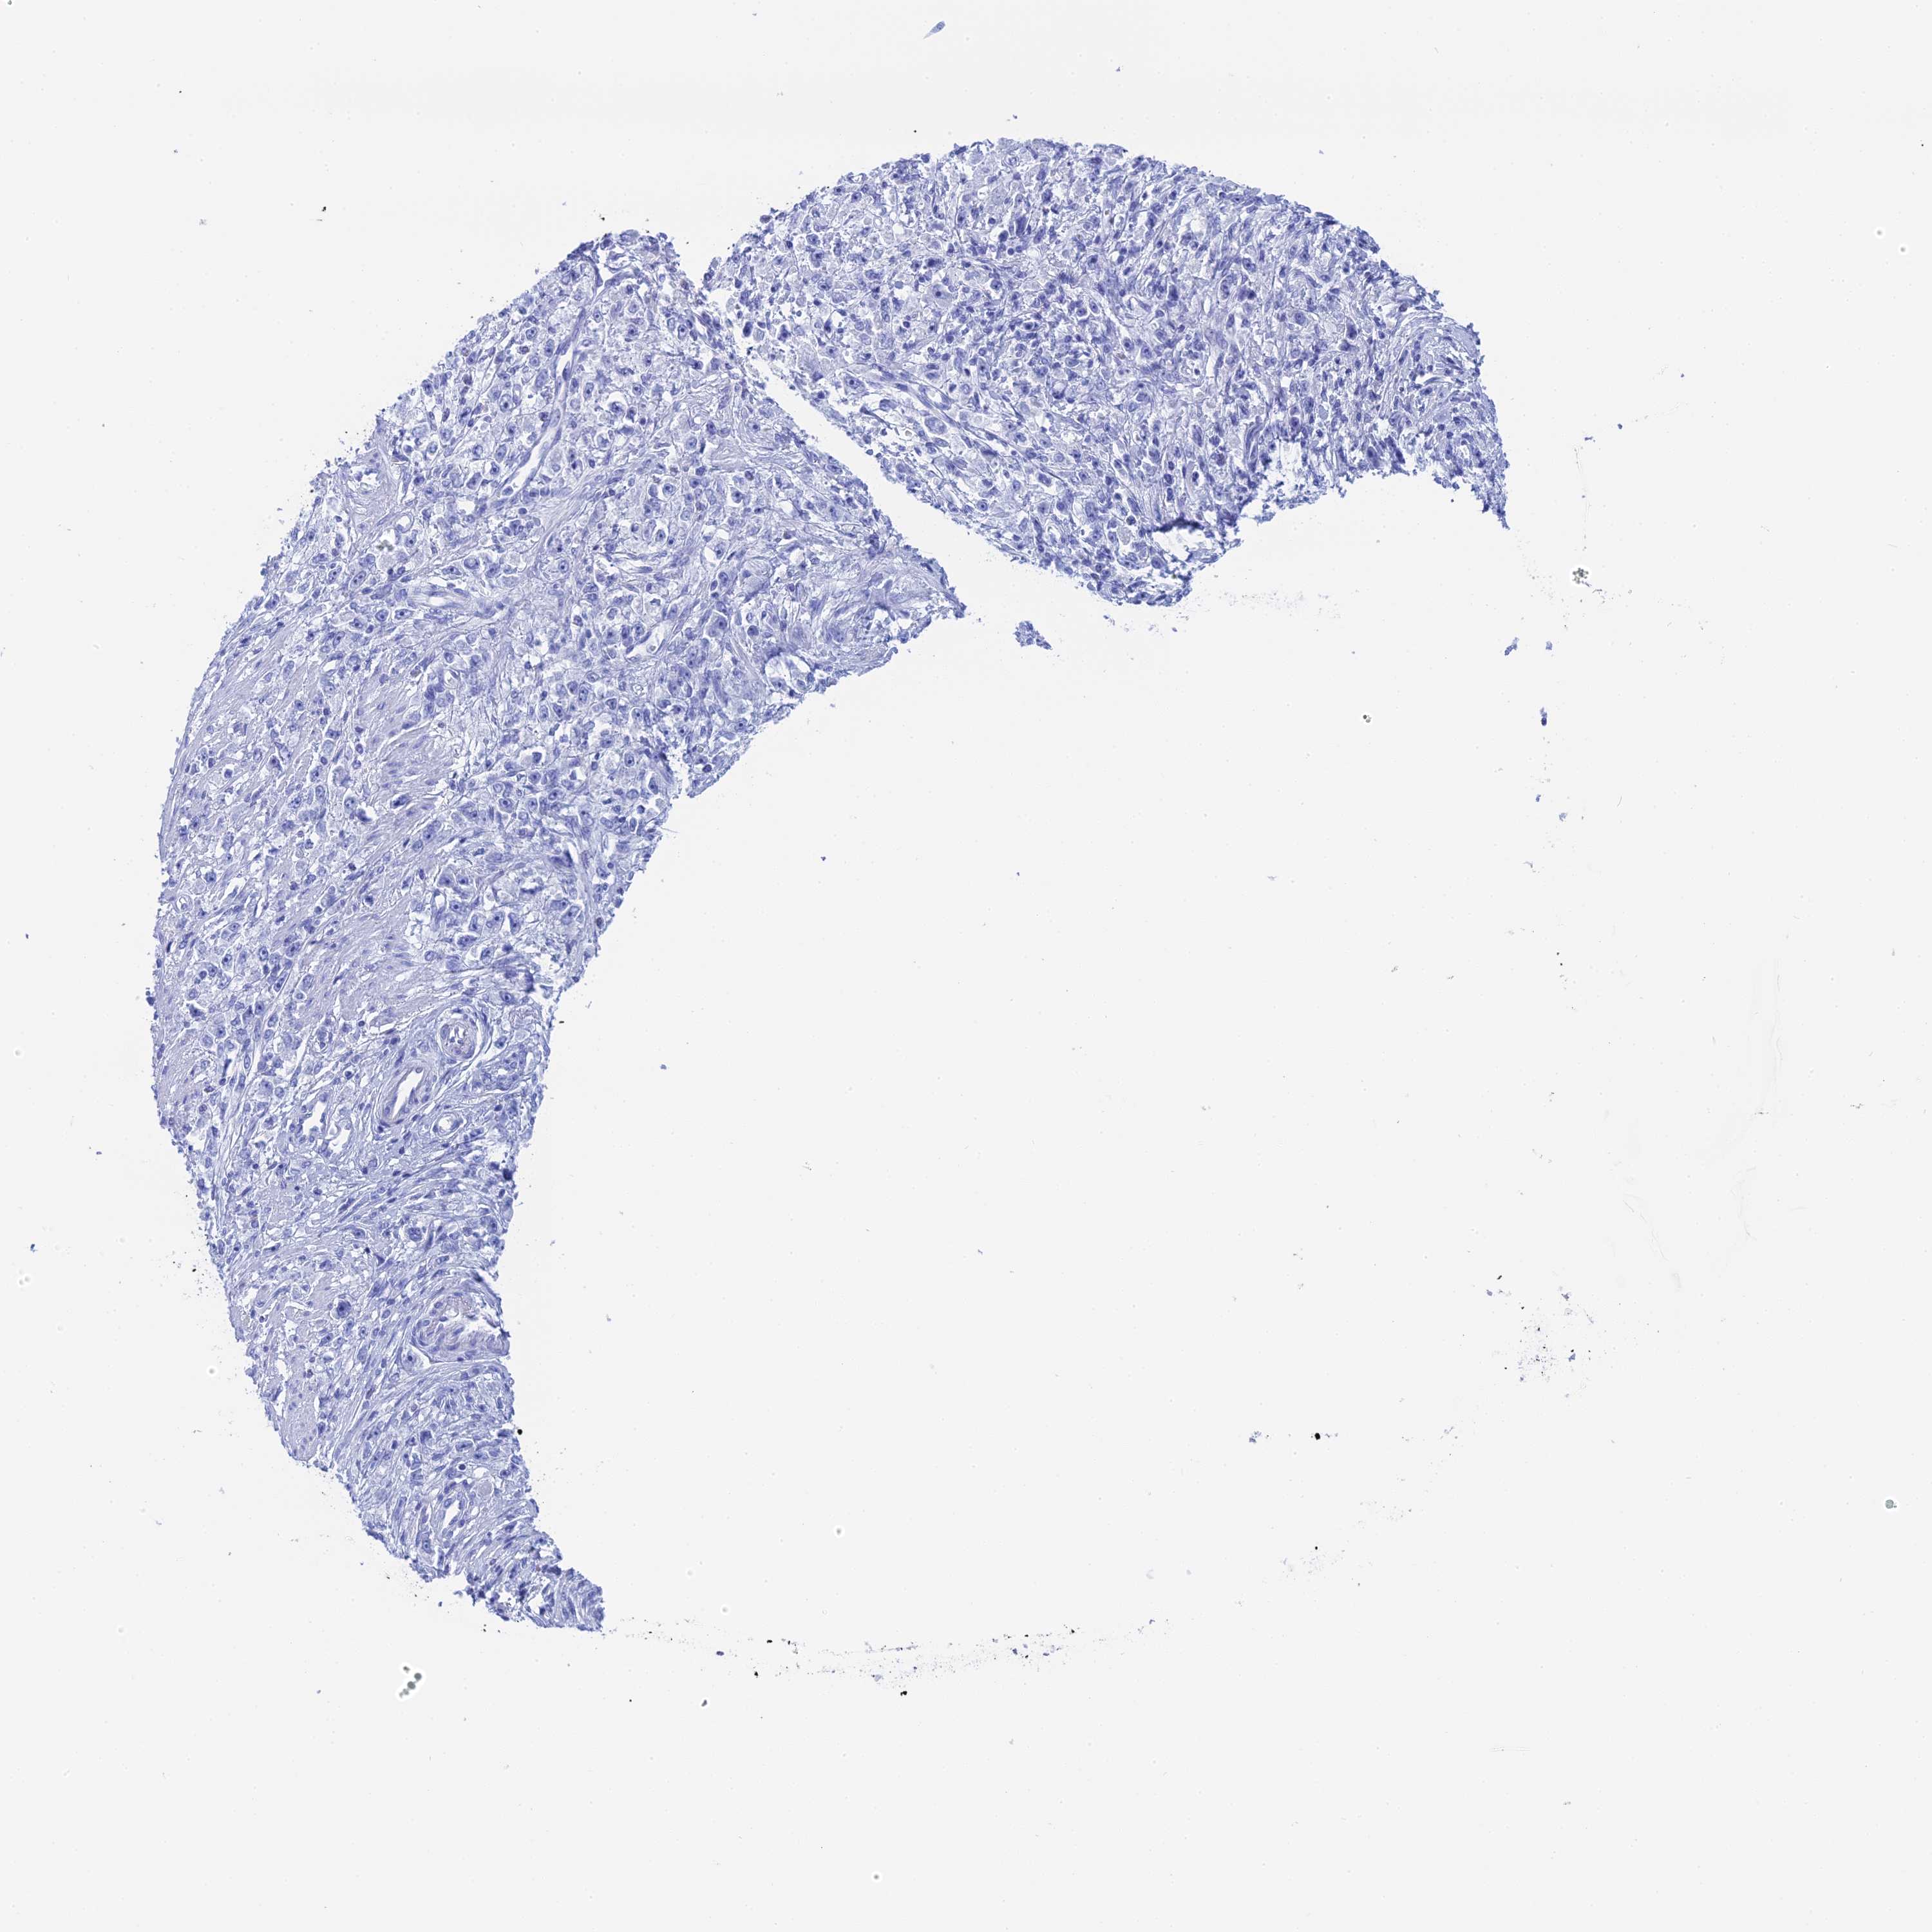

STOMACH CANCER - Protein expressioni

A mouse-over function shows sample information and annotation data. Click on an image to view it in a full screen mode. Samples can be filtered based on level of antibody staining by selecting one or several of the following categories: high, medium, low and not detected. The assay and annotation is described here.

Note that samples used for immunohistochemistry by the Human Protein Atlas do not correspond to samples in the TCGA dataset.

Antibody stainingi

Antibody staining in the annotated cell types in the current human tissue is reported as not detected, low, medium, or high, based on conventional immunohistochemistry profiling in selected tissues. This score is based on the combination of the staining intensity and fraction of stained cells.

Each image is clickable and will lead to virtual microscopy that enables deeper exploration of all samples and also displays staining intensity scores, fraction scores and subcellular localization as well as patient and tissue information for each sample.

Antibody HPA041915

Antibody HPA042513

Staining

High

Medium

Low

Not detected

Adenocarcinoma, NOS